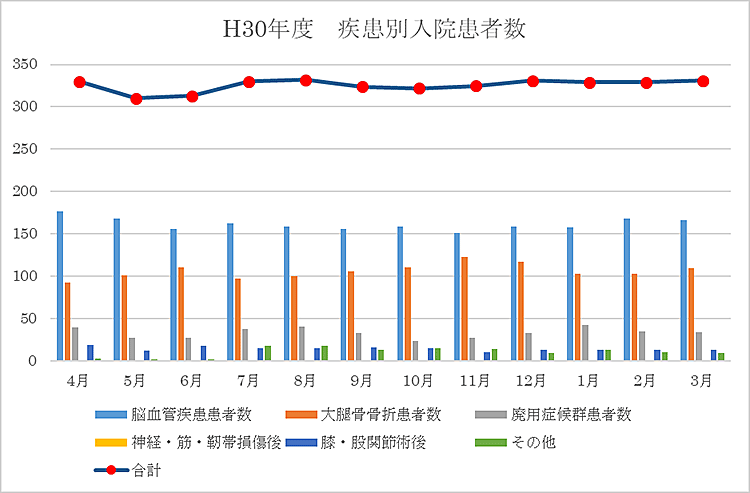

リハビリテーション科の実績

【平成30年度 疾患別入院患者数】